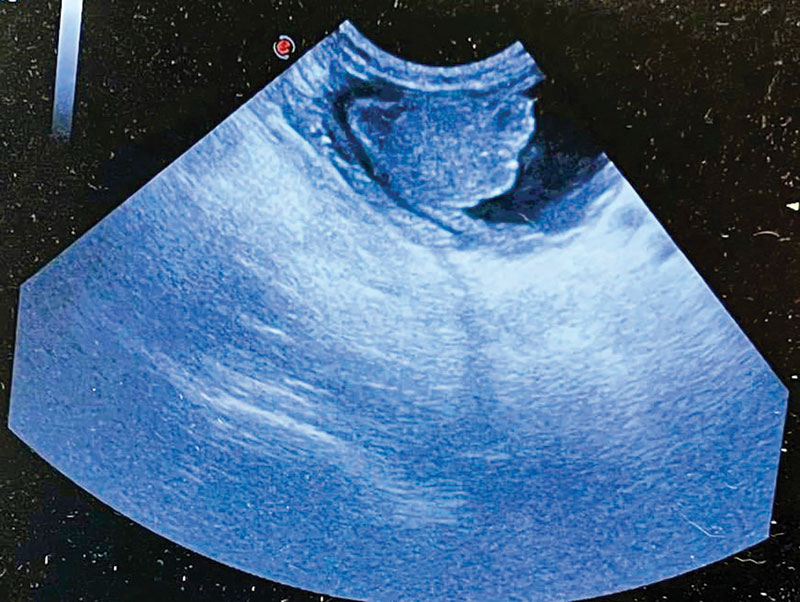

ultrasound image

Using ultrasound in the ER setting

Learn how ultrasound serves as a rapid screening tool for abdominal scans in emergency settings, in this discussion of key techniques and the benefits of incorporating ultrasound into urgent care.